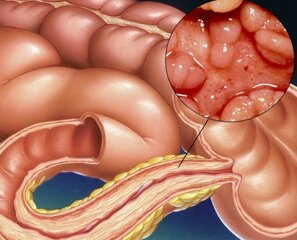

Болезнь Крона представляет собой воспалительное заболевание кишечника, которое сопров Далее...

Болезнь Крона – это хроническое воспаление кишечника, которое впоследствии перерастае Далее...